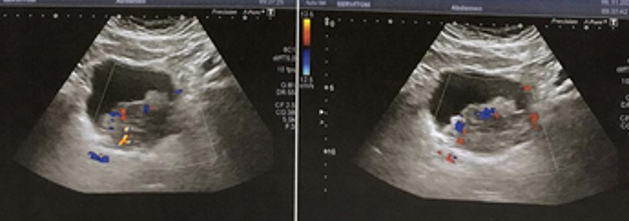

- USG – dilatação bilateral, massa vesical

- Nefrostomia direita com punção guida por USG